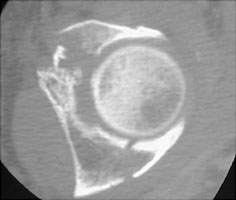

- Click on the image for a larger versionBAxial CT. This image of the right hip at the acetabular level shows the fractures of the anterior and posterior columns.